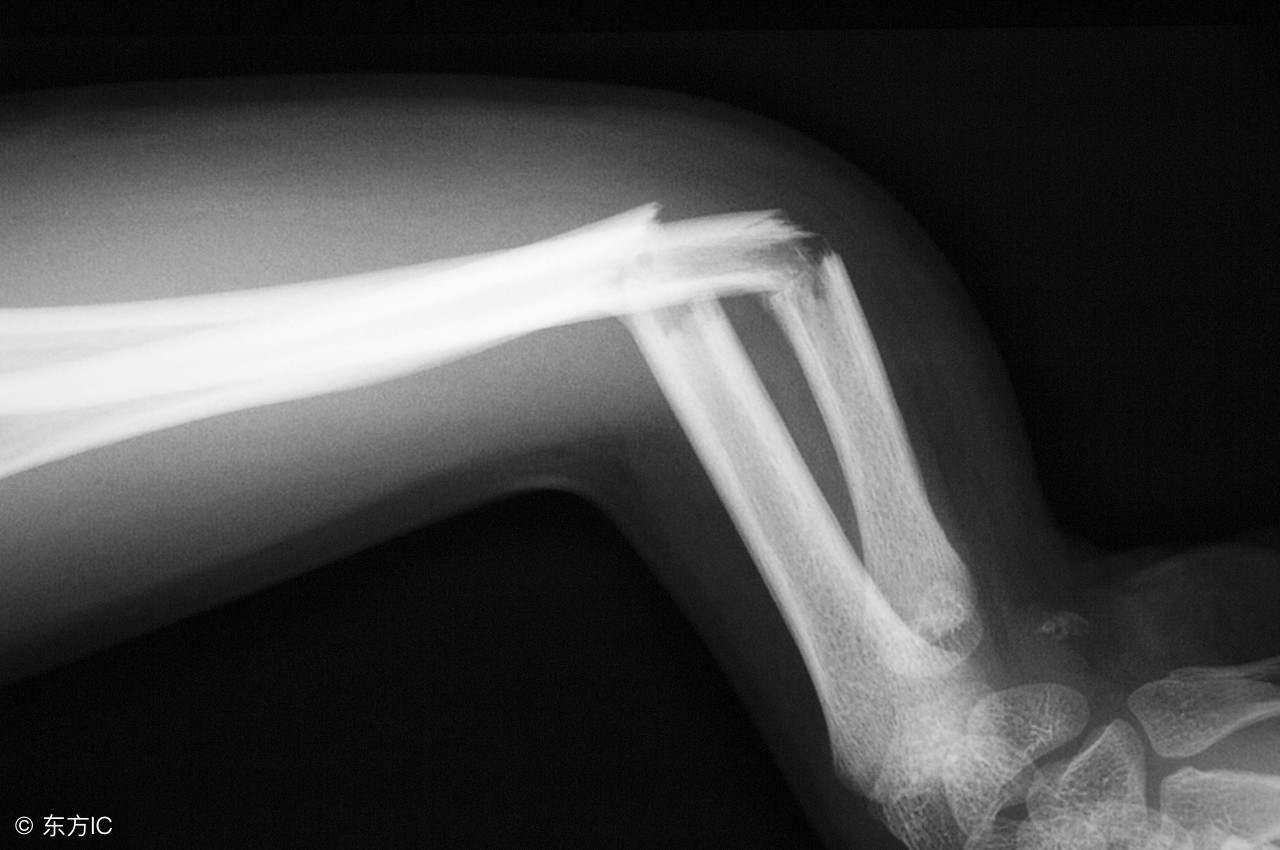

二、骨折

送医院前,不要让骨折部位活动,以免加重伤害,四肢骨折可以寻找树枝、小木板等做成夹板,用来固定骨折部位,在夹板和肢体之间垫上一层毛巾、布之类的东西。*绑捆**夹板的绷带松紧要适宜,绷带位置要超过骨折处的上下两个关节。绑好绷带后,要注意这条肢体的血液循环,注意观察手指、脚趾有没有发紫、发青,以免过紧造成坏死。

如果是脊柱损伤,千万不要一个人抱起患者,要让其平卧在地,让脊椎保持平直,搬运时需要三个人一同,三个人都在患者的同侧,一人托肩背,一人托腰臀,一人托下肢,动作要一致。